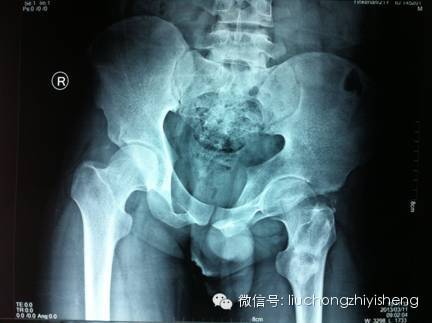

http://mmbiz.qpic.cn/mmbiz/Rk3ictfey1SAelm6MqsaW4ljQkWkaIlnK9fOmyWkn1tYnpeNLgnrOSyq7USDOdCTguMR81Mm00xcyd9azVb133Q/0

如图右侧髋关节处为臀肌挛缩术后异位骨化。